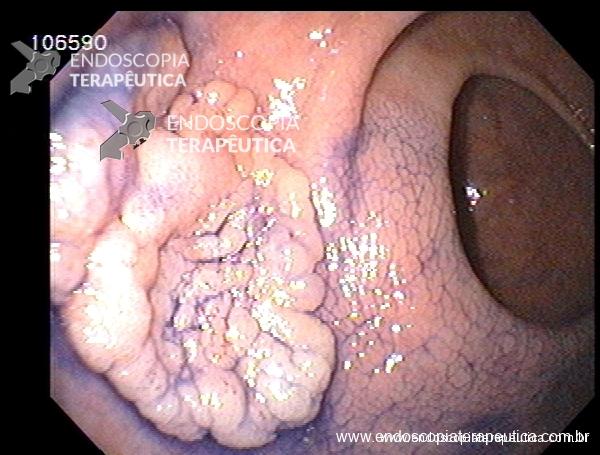

Neoplasia precoce de reto – ESD

Descritores: ESD, Dissecção endoscópica da submucosa, tumor precoce, lesão precoce, neoplasia precoce, early cancer, reto, adenocarcinoma.